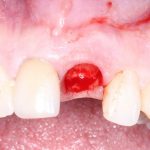

Немедленная имплантация и превентивная аугментация лунки

Как ни странно, но даже после немедленной имплантации происходит атрофия лунки, пусть и в меньшей степени. Особенно это актуально для эстетически значимой зоны — четвёрок, клыков и резцов. Поэтому нередко, одновременно с удалением зуба и установкой имплантата в лунку, мы проводим т. н. «аугментацию лунки», с целью сохранить её форму.

Выглядит это так:

Данная операция проводится с использованием специальных биоматериалов и, повторимся, актуальна для эстетически значимой зоны. Подробнее об этом можно почитать здесь>>